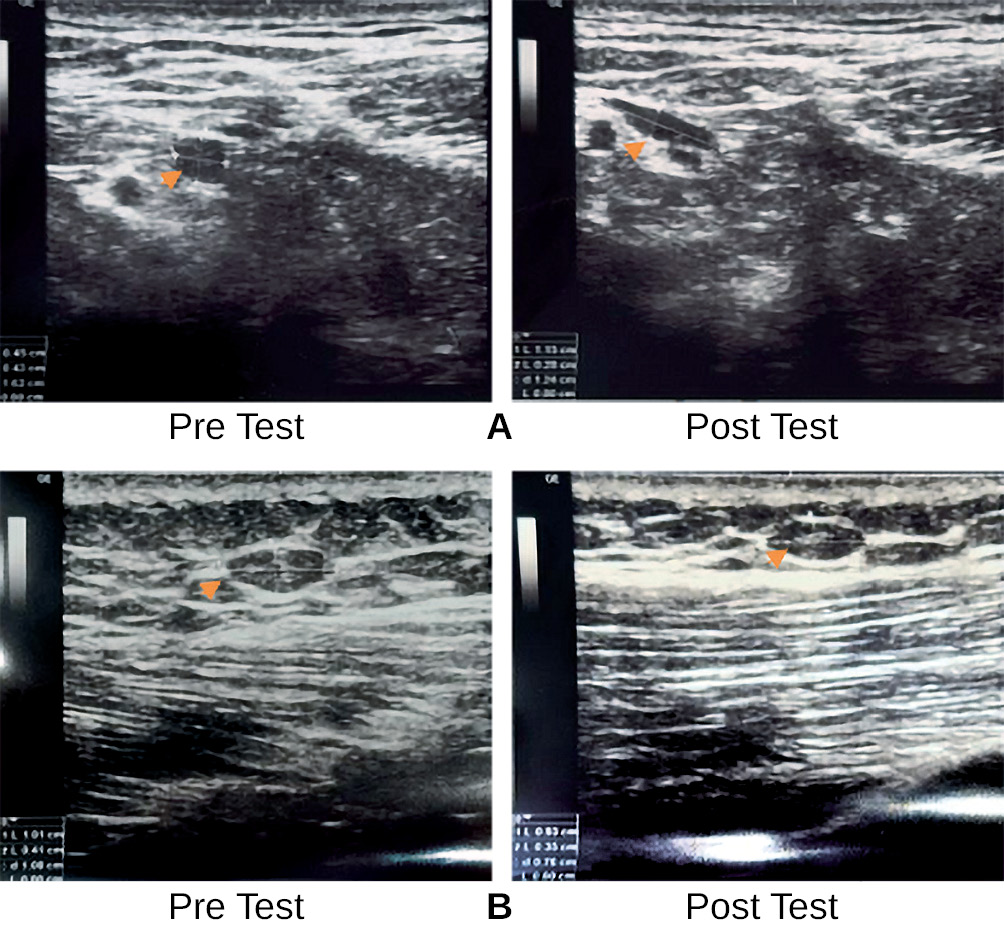

Comparison of pre and post tests and analysis of differences in trigger point size in the Dry Needling and Deep Friction Massage groups

In both the DN and DFM groups, an increase in trigger point size was observed. For the DN group, the mean pre-test size was 0.66 ± 0.8, rising to 0.87 ± 0.1 post-test. Statistical analysis showed no significant changes in trigger point size for this group (p > 0.05). Within 30 minutes post-treatment, 9 participants in the DN group showed a decrease in trigger point size, while 7 showed an increase (Fig. 2).

Fig. 2. Ultrasound Images of Neck Muscles Pre- and Post-Dry Needling Showing Changes in Trigger Point Size

Note: A — presents ultrasonographic (USG) images of the neck muscles captured before and after the dry needling (DN) intervention, showing an increase in trigger point size from 0.45 cm to 1.15 cm; B — displays USG images of the neck muscles obtained pre- and post- DN, highlighting a reduction in trigger point size from 1.01 cm to 0.93 cm.